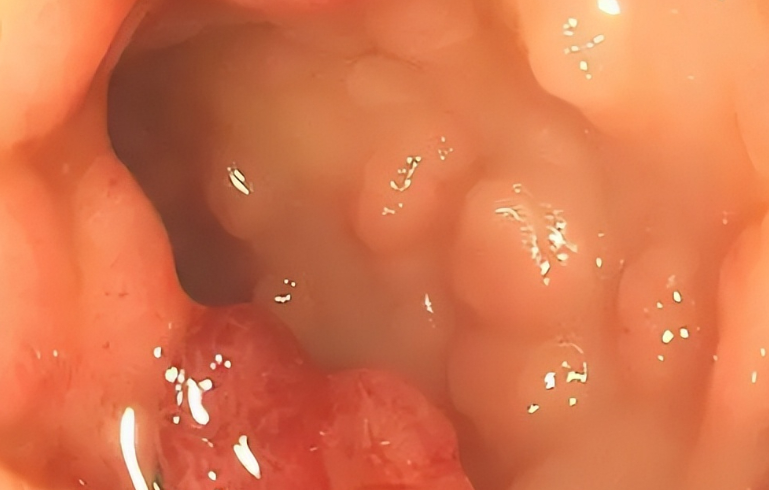

检查结果出来,莉娜的肠道里长了不少息肉。医生告诉她,虽然息肉大多数情况下是良性的,但如果不及时控制,有可能发展成肠癌。接着,医生详细指出了三种可能增加肠癌风险的食物,这些食物都是莉娜日常饮食中常见的。